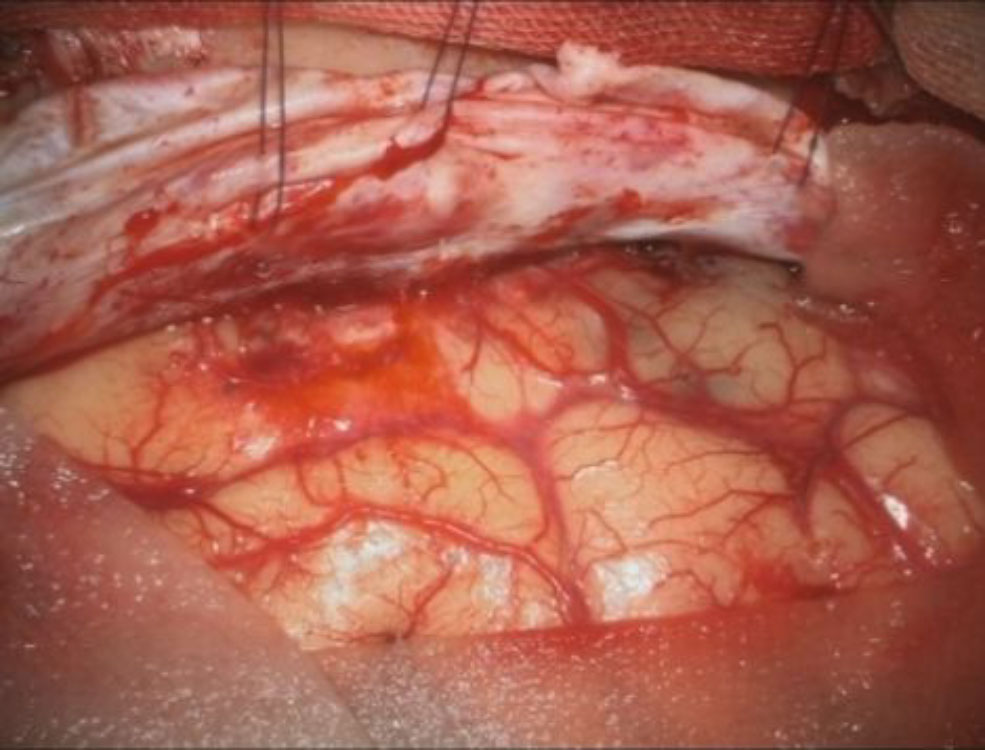

708

'25年12月

60代

左後頭葉腫瘍

頭蓋内腫瘍摘出術

No.’25_110 摘出 前

No.’25_110  摘出 中

No.’25_110 摘出 後